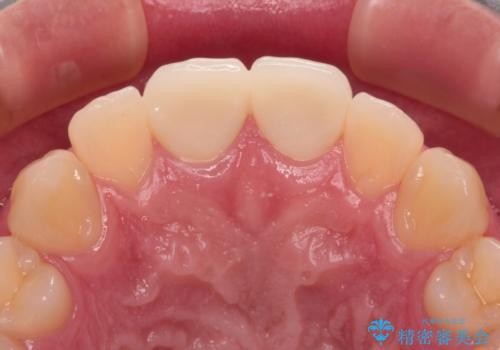

- 酔っ払って転んだらしく、目が覚めたら病室で歯が欠けていたとのことで来院された患者様です。

痛みを感じており、歯の欠けている状況から、神経組織のダメージも想定されました。

無菌的環境下にて歯の状態を調べ、最終的にオールセラミッククラウンにて補綴治療を行うこととしました。

幸いにも神経組織に影響はなく、健全な状態で治療を終えることができました。

歯肉の腫脹が目立っていたため、衛生指導も並行して行い、引き締まった歯肉になりました。